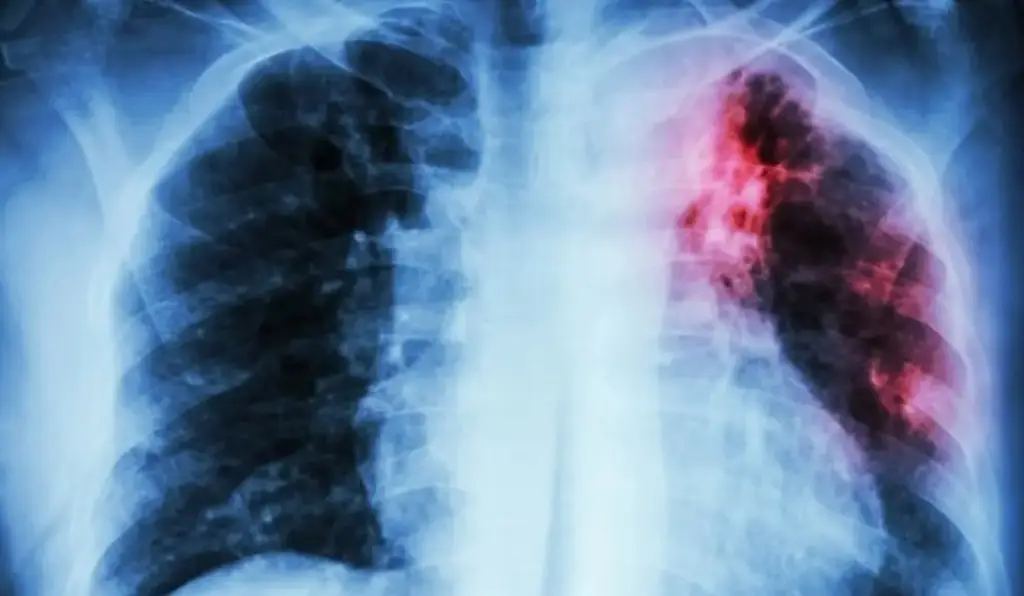

Indicó que la tuberculosis, va destruyendo el pulmón y puede generar insufiencia respiratoria, es decir, el paciente a la larga va a tener falta de aire si no se trata la enfermedad de forma correcta.